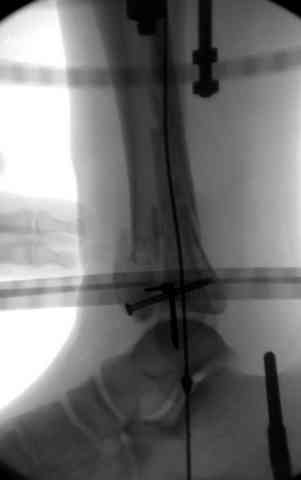

Яков изложил все необходимые аспекты лечения переломов пилона, и, не желая менять тему, решил выставить нашу точку зрения в двух клинических примерах.

При лечении внутрисуставных переломов типа "Pilon"

или "Tibial Plateau" на голени, применение простых

наружных фиксаторов типа "Spanning ExFix" или "Travelling ExFix" стал одним из стандартом этапного лечения.

В первые часы после поступления больным экстренно накладывается простой фиксатор из двух поперечно проведенных стержней или сооружается "Delta

Frame" в зависимости от места локализации, и проводится дистракция.

Здесь выставлена пара случаев перелома пилона, оба

случая леченные этапным наружным фиксатором.